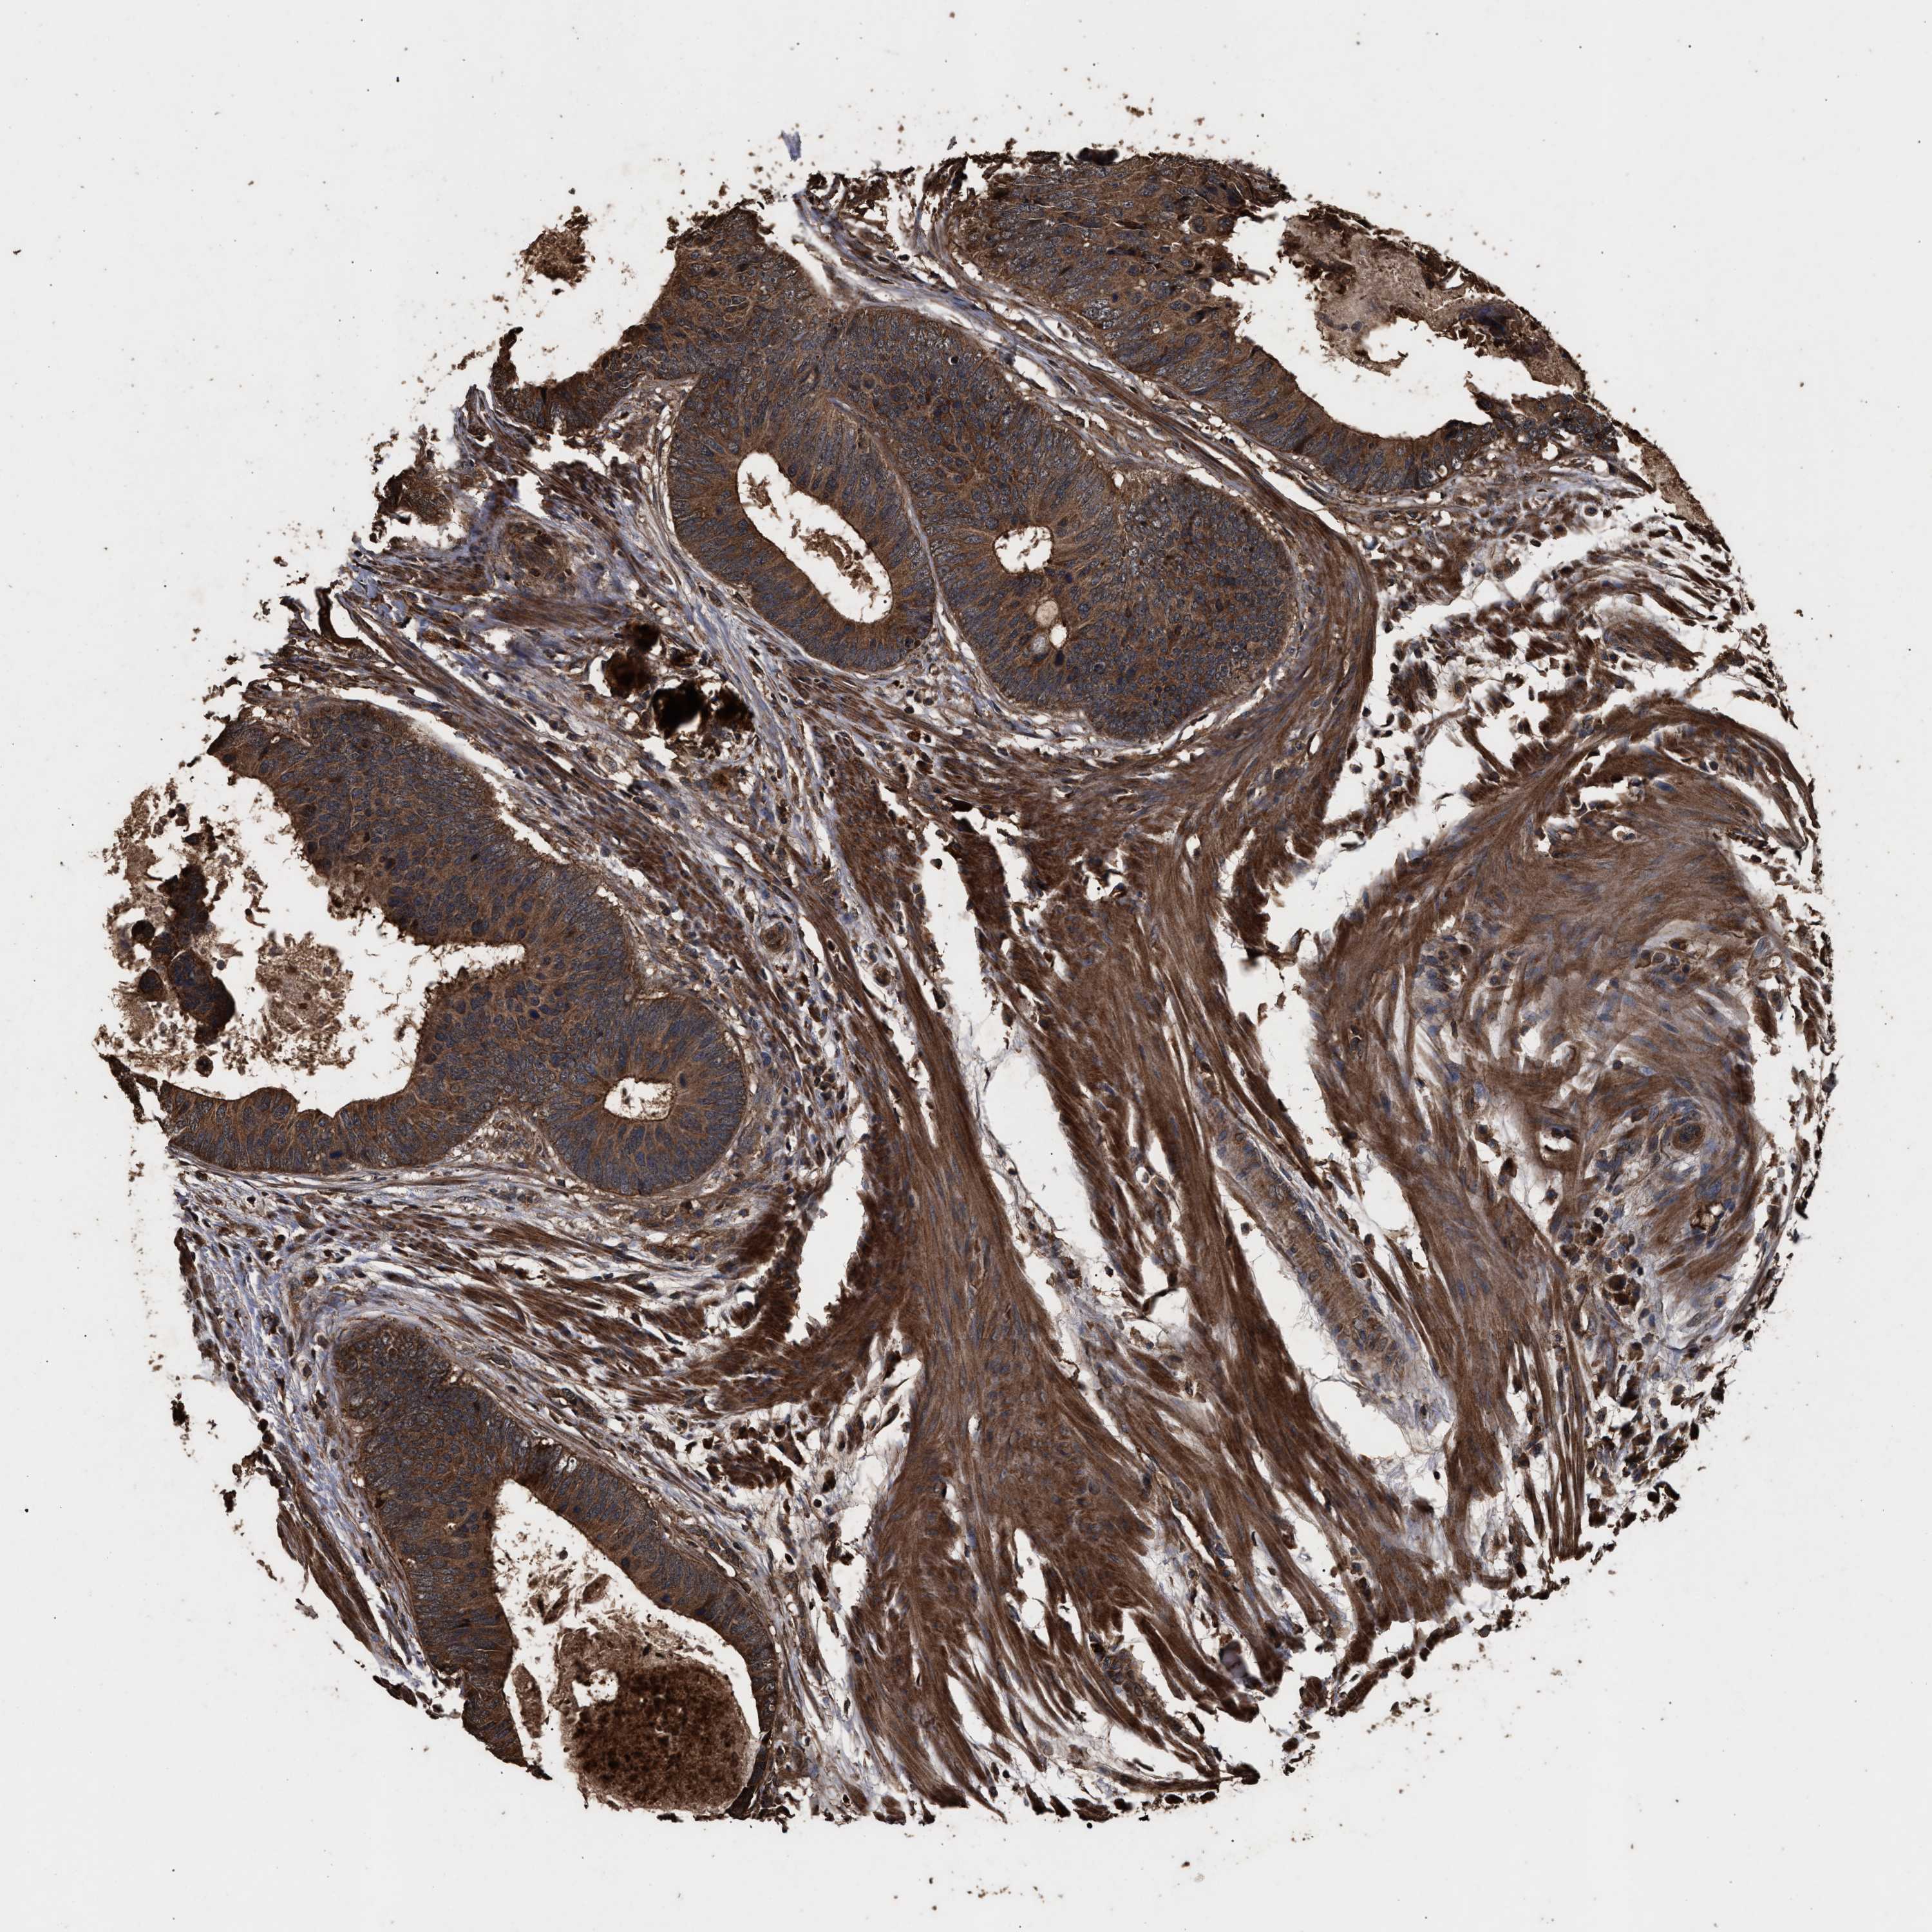

CANCER COLORECTAL CANCER Show tissue menu

Colorectal cancer

Human cancer

Rectum adenocarcinoma